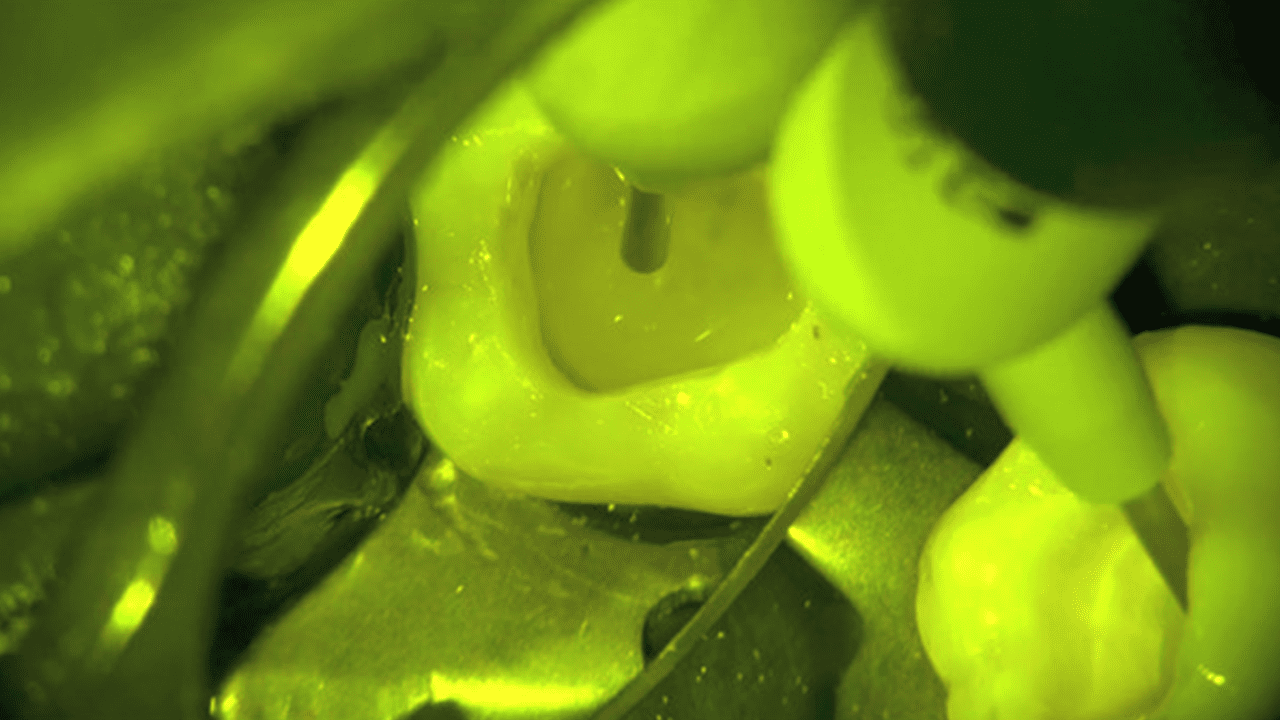

How does SDR Plus provide reliable adhesion and a tight seal to protect the proximal box? Here is how this bulk fill composite allows dental practitioners to place gap-free restorations:

Start at the bottom of the box, slowly withdraw tip, wipe tip across cusp and allow to self-level for a few seconds. Do not use an instrument to manipulate as this can disturb the self-leveling behavior of the materials.